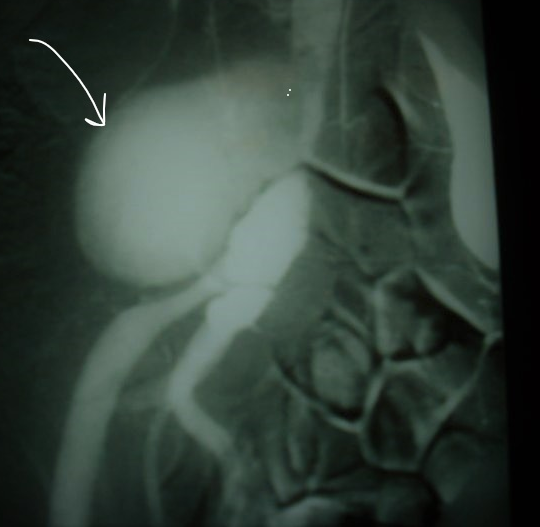

Anévrisme de l’artère iliaque primitive droite

Il s'agissait d'un patient âgé de 55 ans, ses antécédents étaient marqués par une aphtose buccale récidivante, il était hospitalisé pour une douleur pelvienne d'installation brutale et chez qui, l'examen clinique trouvait une masse pelvienne sensible, pulsatile et soufflante à l'auscultation évoquant une origine vasculaire, l'examen des organes génitaux externes trouvait une cicatrice d'aphtose scrotale. Le bilan biologique objectivait un syndrome inflammatoire avec CRP à 80 mg/l, la sérologie syphilitique était négative, l'écho-doopler pelvienne était faveur d'un anévrisme de l'artère iliaque primitive droite et l'artériographie confirmait le diagnostic Le diagnostic de la maladie de Behçet était retenu devant l'aphtose bipolaire et l'atteinte vasculaire. Le traitement comportait une exérèse chirurgicale de l'anévrisme, corticothérapie en bolus de trois jours puis en relai par voie orale et une perfusion mensuelle de cyclophosphamide. L'évolution était favorable.